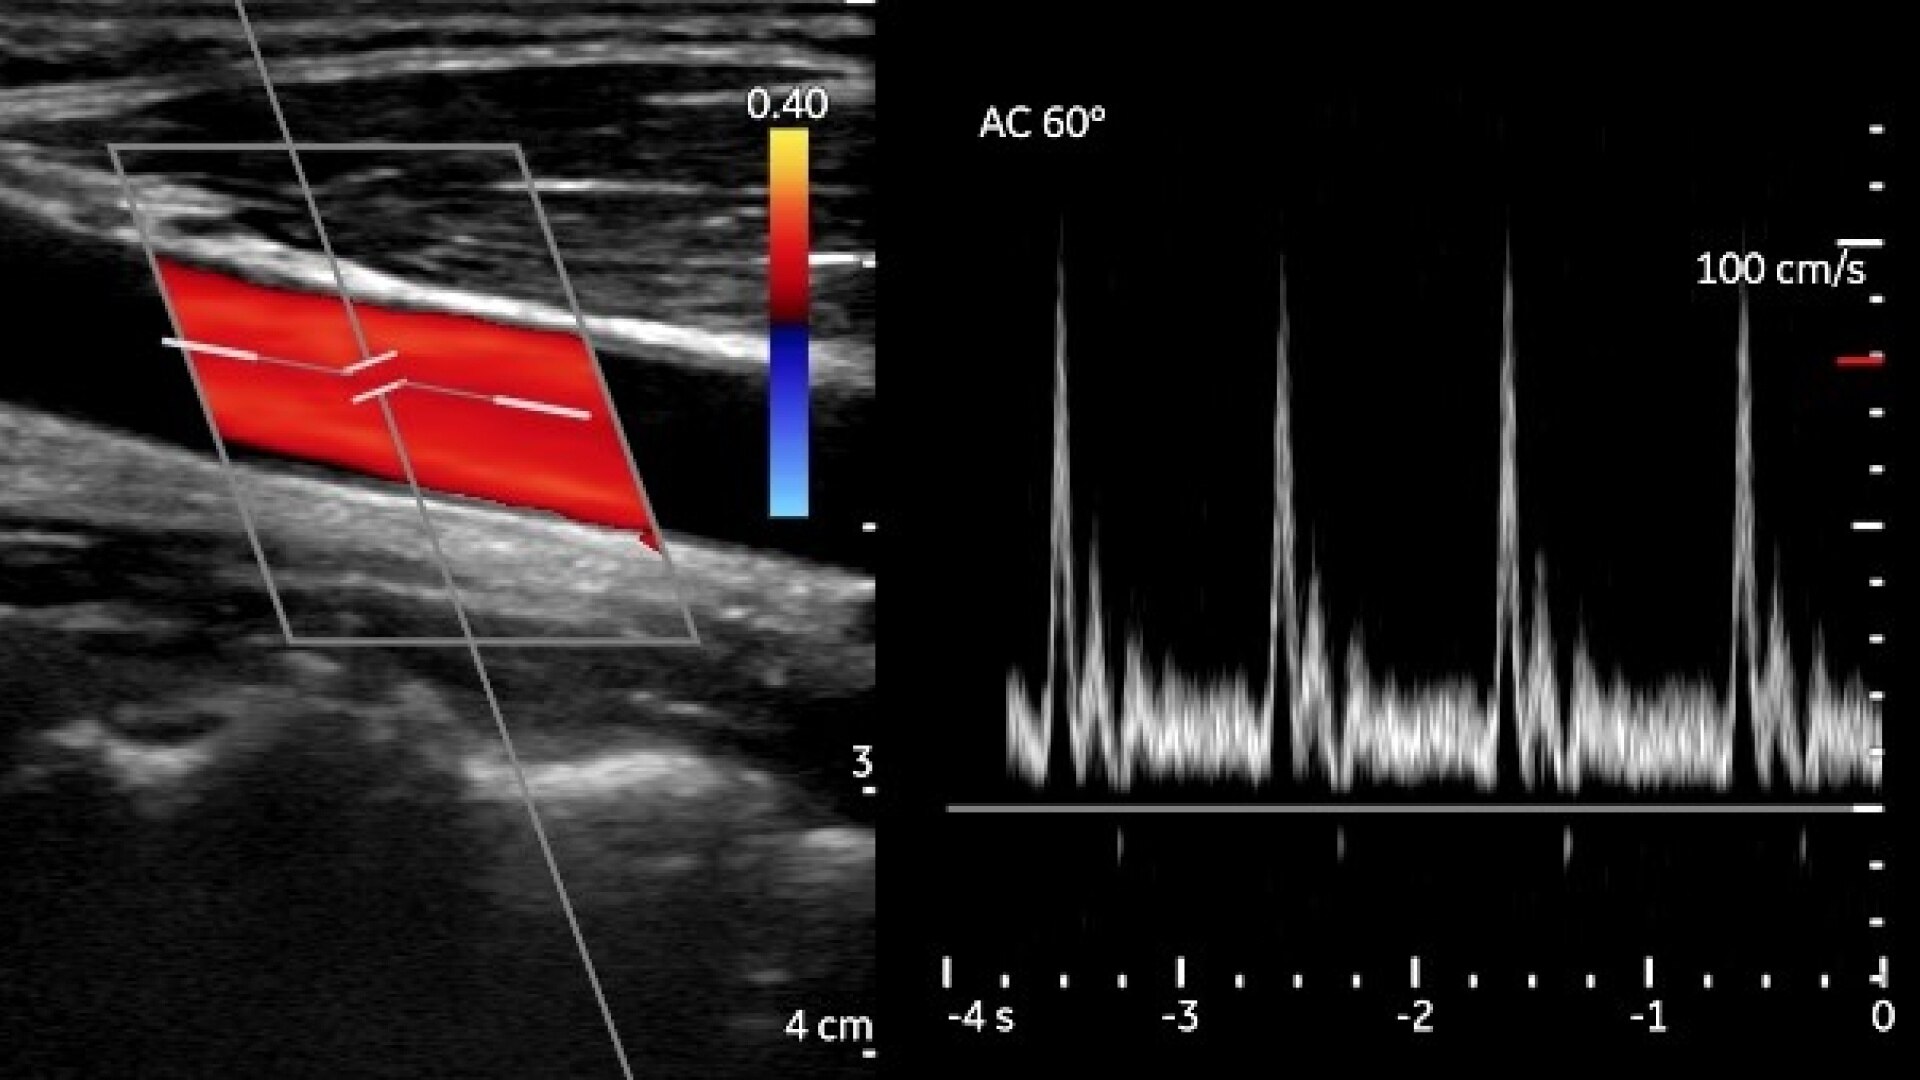

The fastest and most accurate follicular monitoring tool utilizing AI to standardize measurements, support clinical decisions and provide workload prediction for your clinical, embryology and administrative staff.

• Allows for 2 minute monitoring exams from any 3D Voluson enabling REIs to review ovarian and uterine videos anywhere, any time in the mycycleclarity portal. Follicular measurements are transmitted seamlessly to your EMR.

Cycle Clarity aims to revolutionize reproductive healthcare globally through cognitive computing. Their innovative software employs a recurrent neural network to provide accurate follicle measurements with a quick 10-second 3D ovarian ultrasound. Measurements are seamlessly transmitted to the EMR, and the MyCycleClarity portal offers access to data, including raw and annotated ultrasounds, and analytics for optimal oocyte retrieval timing, enhancing clinical decision-making.